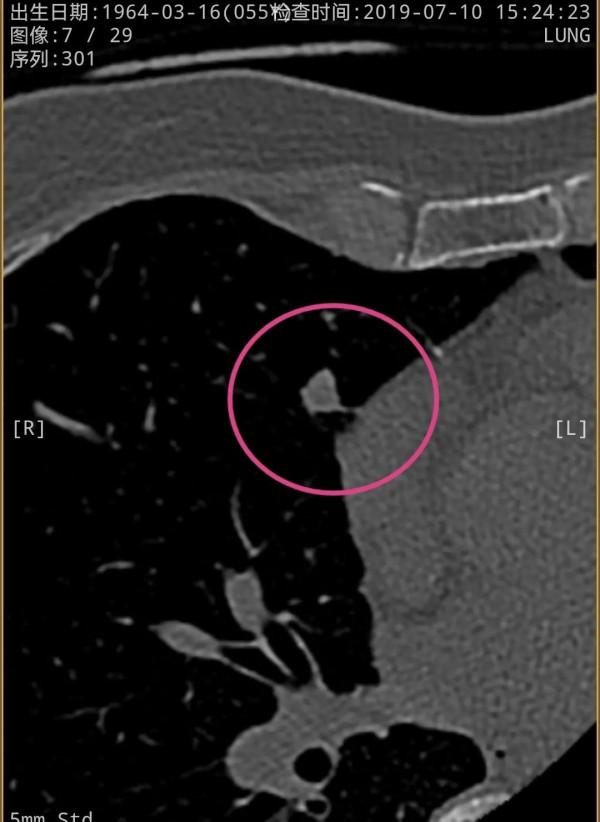

我們先來看2021年12月的,右肺多發實性結節,邊緣相對平直,膨脹性不明顯,紅色圈起來的主病灶周邊一圈密度高,中間密度低,還有點狀高密度,考慮肉芽腫性炎伴壞死(區域性纖維鈣化),次病灶藍色圈起來的形態也是類似的,骨窗看也是中間密度低,而周邊一圈密度高。那麼再來看2019年時是如何的呢?假如是惡性,應該有進展。但我們閱片後發現並沒有大的變化,由於掃描條件不同,中間密度低在平掃上不明顯,紫紅圈起來的和綠色圈起來的分別對應主病灶和次病灶。但當時有區域性靶掃描,結果形態與2年後的沒什麼區別,當時也已經是周邊一圈密度高,而中間密度低且均勻。所以此兩灶可基本認定為肉芽腫性炎伴壞死,可安全隨訪。最好半年查一次(因為正常沒結節也一年查一次呢)。